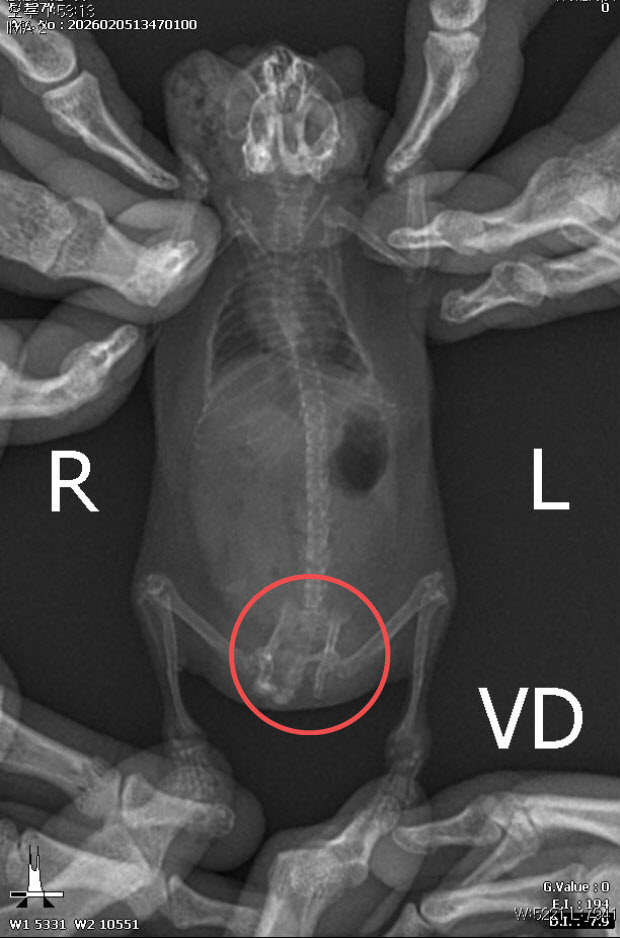

정글리안 햄스터의 골반이 골절된 흔적. (사진=동물자유연대 제공)

이어 “귀가 찢어지는 등 다수의 개체에서 교상 흔적이 관찰됐으며 일부 개체는 장기간 반복된 타박상으로 인해 골절 및 재골절이 의심되는 정황까지 확인됐다”고 덧붙였다.